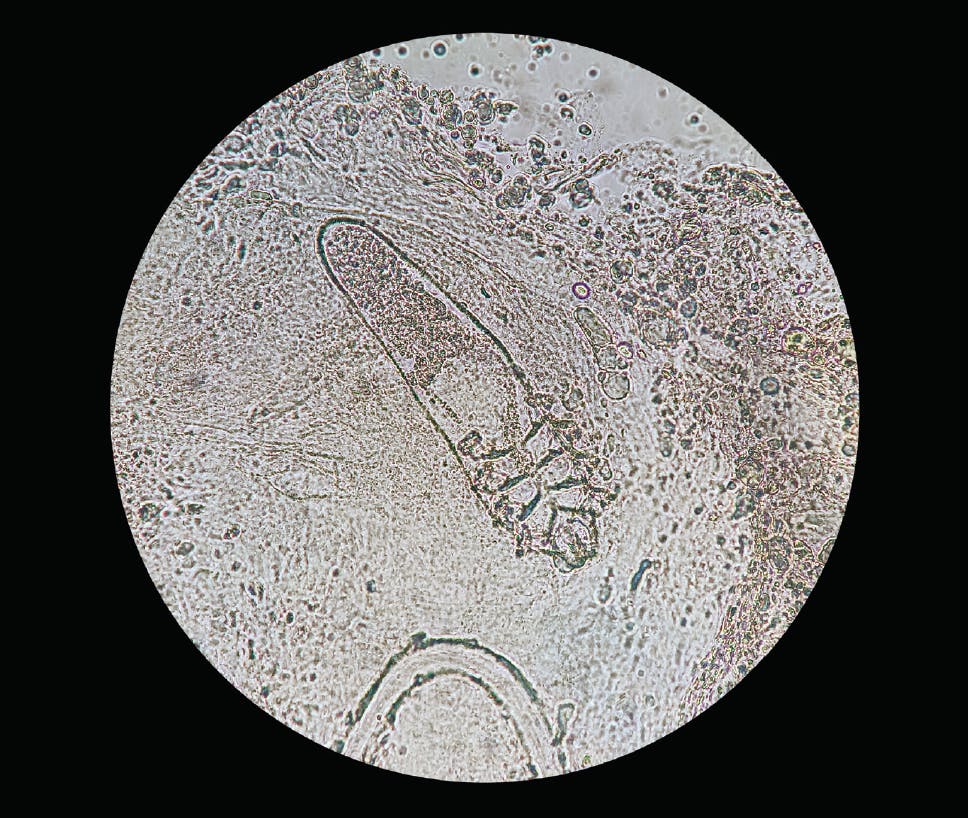

A BREAKTHROUGH IN MANAGING DEMODEX?

Demodex mites (Figure) are a common cause of blepharitis, implicated in approximately 45% of chronic cases.12 The clinical finding of cylindrical dandruff is pathognomonic. In one study, 100% of lashes with cylindrical dandruff were found to have Demodex mites.13 Standard treatments include lid hygiene products containing tea tree oil and oral ivermectin.14 A new topical formulation that causes paralysis and death of Demodex mites (TP-03, Tarsus Pharmaceuticals) is under investigation. Phase 2 studies have shown that a 6-week course of twice daily dosing of TP-03 cured 70% to 80% of patients.15

A phase 2b/3 trial is under way.16 If approved, TP-03 would likely be the first prescription agent specifically indicated for the treatment of Demodex blepharitis.